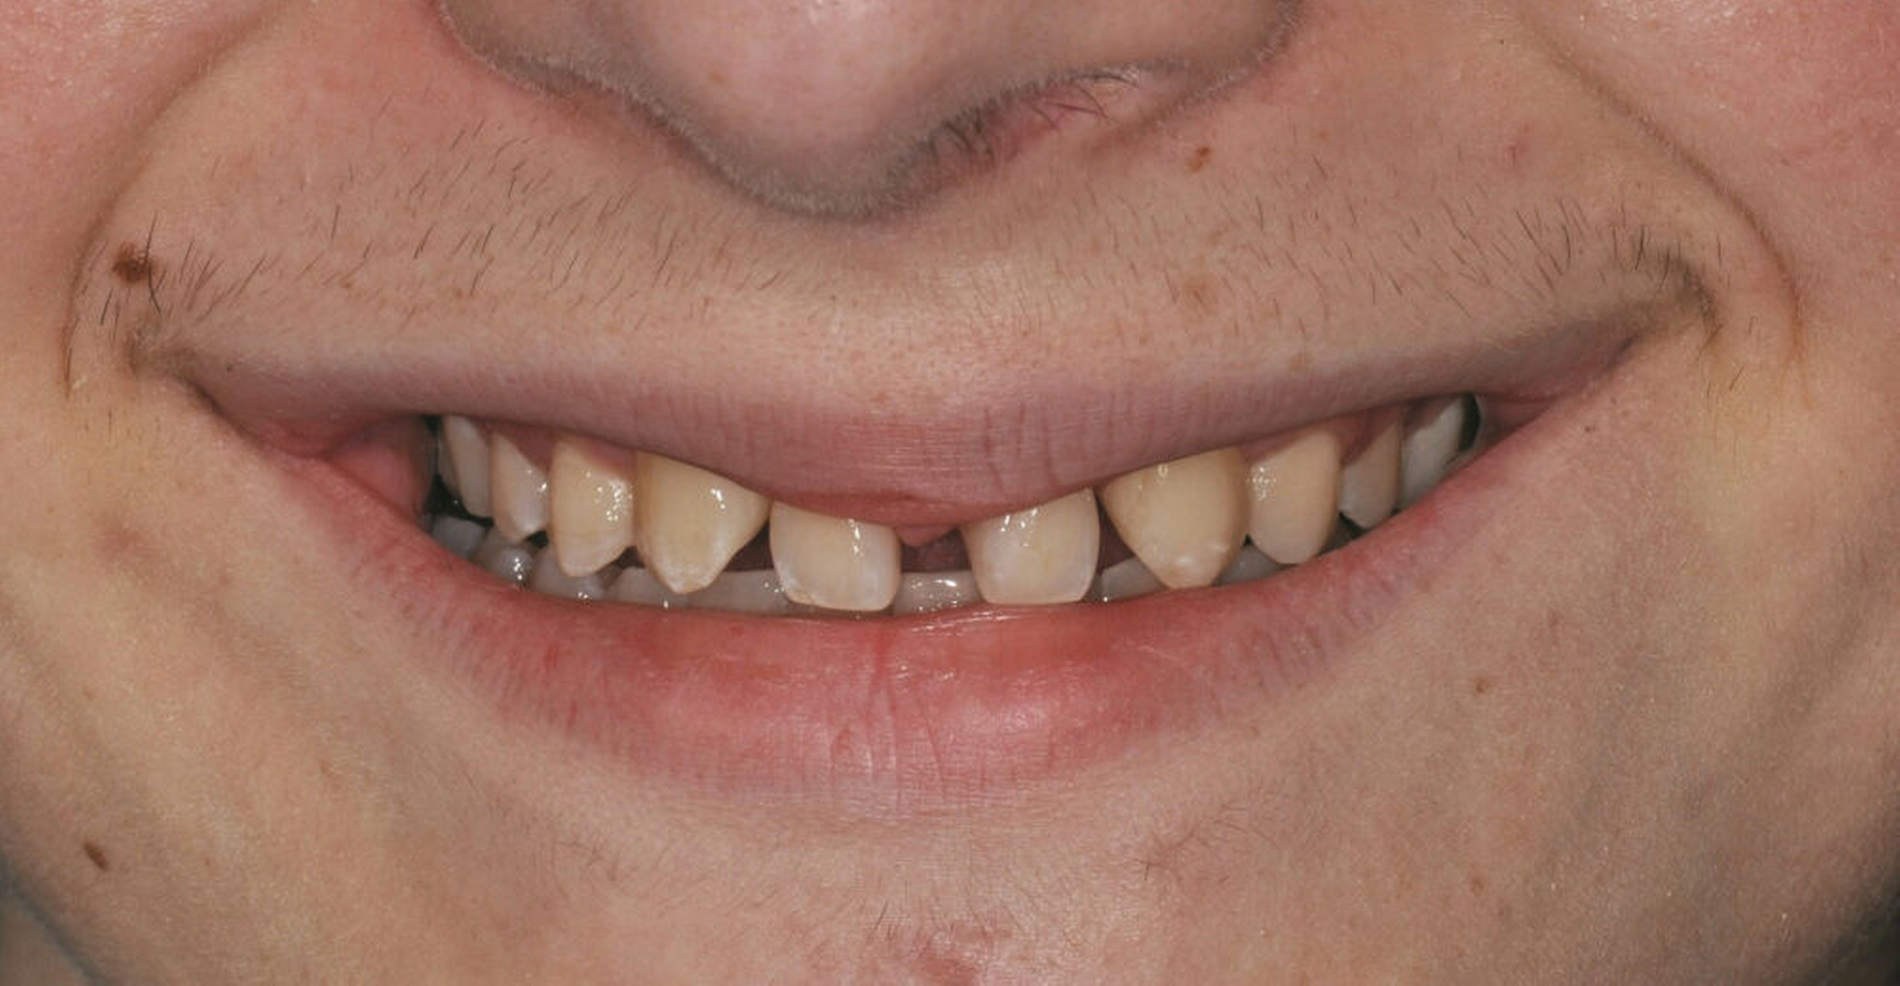

Bei der Erstvorstellung zeigt der Patient ein ausgeprägtes Diastema mediale sowie Restlücken und Asymmetrien im Oberkieferfrontzahnbereich nach kieferorthopädischer Therapie alio loco (Abbildung 1). Aufgrund mangelnder Adhärenz konnten nicht alle kieferorthopädischen Behandlungsziele erreicht werden, was insbesondere aus ästhetischer Sicht Herausforderungen für den restaurativen Lückenschluss mit sich bringt. Erschwerende Faktoren sind die Verschiebung der Mittellinie, die Achsenneigung der Zähne 13, 12, 22 und 23 sowie die inhomogene Lückenverteilung mit ungleich verteilten Lückengrößen (Abbildung 2). Eine erneute kieferorthopädische Korrektur lehnt der Patient allerdings ab. Subjektiv empfindet er insbesondere das kindliche Erscheinungsbild der lückig stehenden, kurz und klein wirkenden seitlichen Schneidezähne als störend. Ziele der Behandlung sind eine präventionsorientierte, ästhetisch-funktionale Rehabilitation des Oberkieferfrontzahnbereichs und eine Harmonisierung des dentofazialen Erscheinungsbildes.